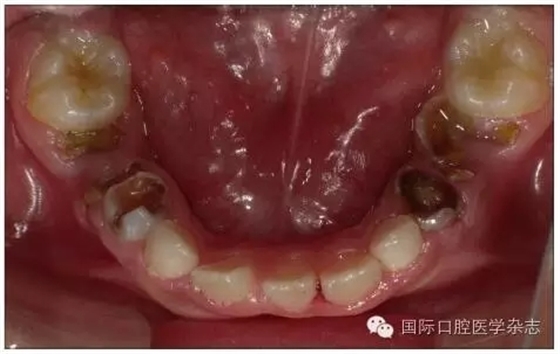

1.1.3 對(duì)牙弓長(zhǎng)度的影響 乳牙齲病引起牙弓長(zhǎng)度的變化并不只在乳牙因齲早失后,而是在乳牙發(fā)生鄰面齲之時(shí)即可發(fā)生。乳磨牙及乳尖牙鄰面的齲壞可引起牙冠近遠(yuǎn)中徑縮窄,造成鄰牙向缺隙處移動(dòng)、牙弓長(zhǎng)度開始減?。▓D1),這樣會(huì)引起日后恒牙列的擁擠與牙列不齊。在兒童口腔健康管理的理念指導(dǎo)下,應(yīng)盡早治療乳牙齲病,特別是乳磨牙鄰面齲,盡量恢復(fù)患牙的外形和咀嚼功能,維持牙弓長(zhǎng)度。對(duì)因齲壞牙而導(dǎo)致牙弓縮短的病例,可行間隙擴(kuò)大矯治器(space regain appliance)以恢復(fù)牙弓長(zhǎng)度,避免日后牙列擁擠的出現(xiàn)或減輕擁擠程度[2]。

圖1 下頜第一、第二乳磨牙重度齲壞,牙弓長(zhǎng)度減少

Fig 1 Severecaries of the first and second mandibular primary molar intraoral arch length lessened